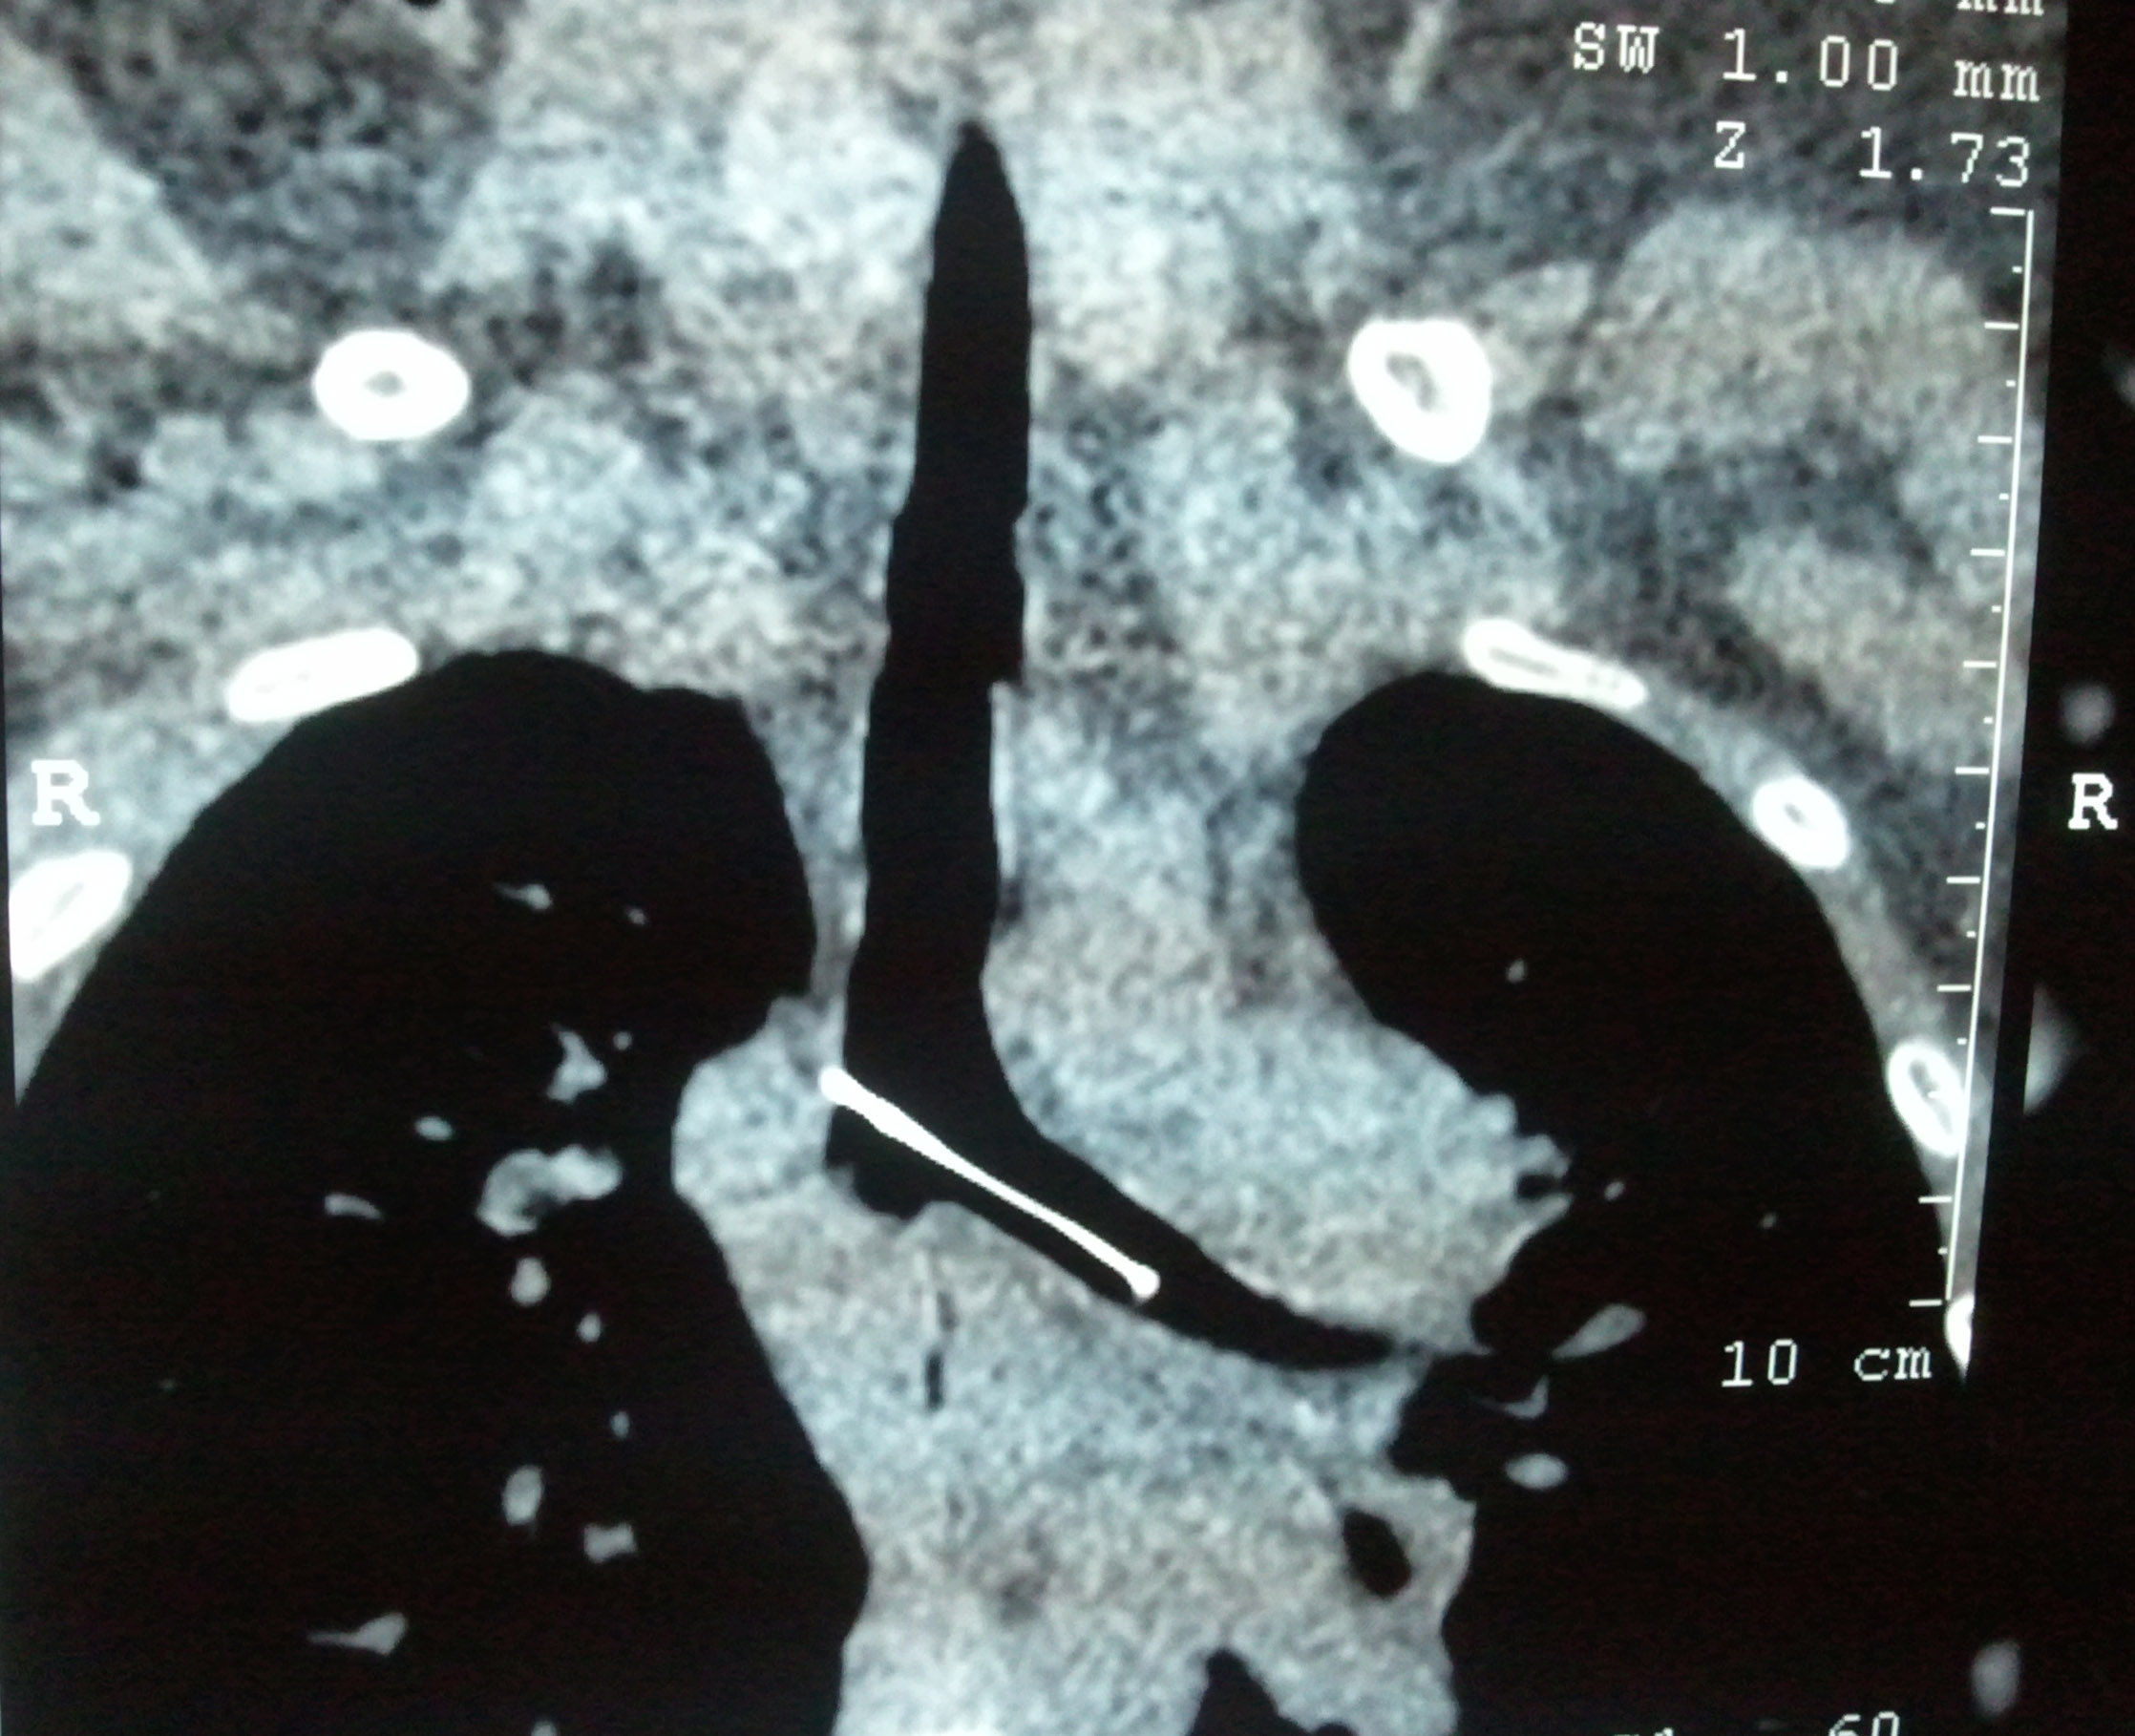

胸部ct:主气管针形金属异物,针尖已经扎入主气管右侧壁

都是气管内异物惹的祸